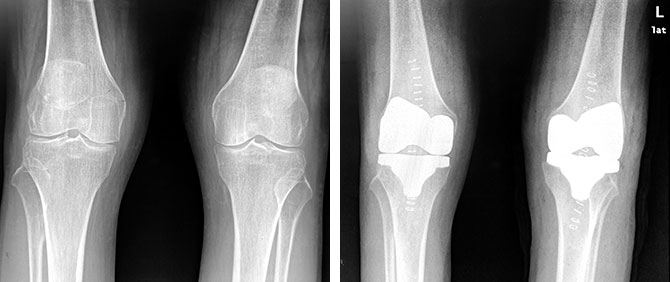

MAKO机器人辅助下的人工全膝关节置换手术前,科室团队将患者膝关节螺旋CT扫描数据进行三维重建,通过智能骨科手术系统对患者的膝关节骨骼形态、间隙平衡的评估,设计出最适合患者的手术方案。5台手术分别在郑秋坚主任和马元琛主任带领的机器人手术团队的合作下顺利完成,其中一位患者更是接受了难度更高的同期双侧机器人全膝关节置换手术。术后影像学结果显示,假体大小、位置、角度都精确地重现了术前的计划,达到了精确重建膝关节的目标。患者对手术效果十分满意。

患者术前(左图)术后双膝关节X线对比